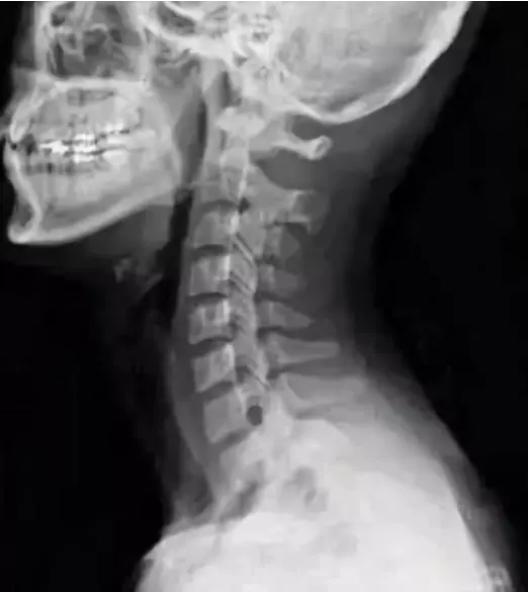

大家都知道,颈椎的正常生理曲度是前凸的,而胸椎是后凸的。在颈胸交界刚好是前凸后凸的交界,当颈椎下段过度前凸而胸椎上段过度后凸时就形成了骨性的颈胸交界骨性突起。

正常的颈椎图

这样的骨性突起直接影响到附着的肌肉,相关的肌肉群也会因此紧张痉挛而肿胀,两边的第一第二肋骨也因此而翻转,椎肋间的肌肉群肿胀痉挛,甚至翻转的肋骨还波及斜角肌以至于斜角肌间隙变得狭窄。这样肌肉的肿胀使得这个骨性的突起变大并且更加突出,"富贵包"就此成型。